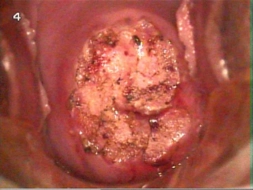

rahim ağzı yarası nasıl geçer bitkisel yöntemler ile ilgili bilgi arıyorum. Daha önce bitkisel çözümler denedim ama etkisi sınırlı oldu. Aloe vera ve zerdeçalın yararlı olduğunu duydum. Bu konuda deneyimi olan var mı, hangi yöntemler daha etkili? Yorumlarınızı bekliyorum.

Rahim ağzı yarası gibi hassas bir konuda bitkisel yöntemler denemek, birçok kişi için çekici olabilir. Ancak, bu tür rahatsızlıkların tedavisinde her zaman uzman bir doktora danışmak en sağlıklı yoldur. Bitkisel çözümler bazı kişilerde fayda sağlasa da, etkileri kişiden kişiye değişebilir ve bazı durumlarda yarardan çok zarar verebilir.